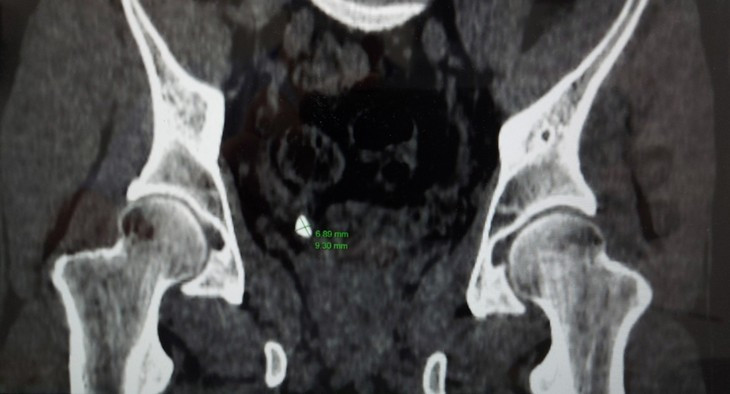

Ngay lập tức, người bệnh được các bác sĩ chỉ định làm các xét nghiệm, siêu âm bụng, chụp cắt lớp vi tính và xác định người bệnh bị sỏi niệu quản phải 1/3 dưới (nằm ở vị trí đoạn nối của niệu quản khi vào tới bàng quang), sỏi kích thước xấp xỉ 9x7mm.

Sỏi thận trong cơ thể người bệnh trên phim chụp - Ảnh BVCC